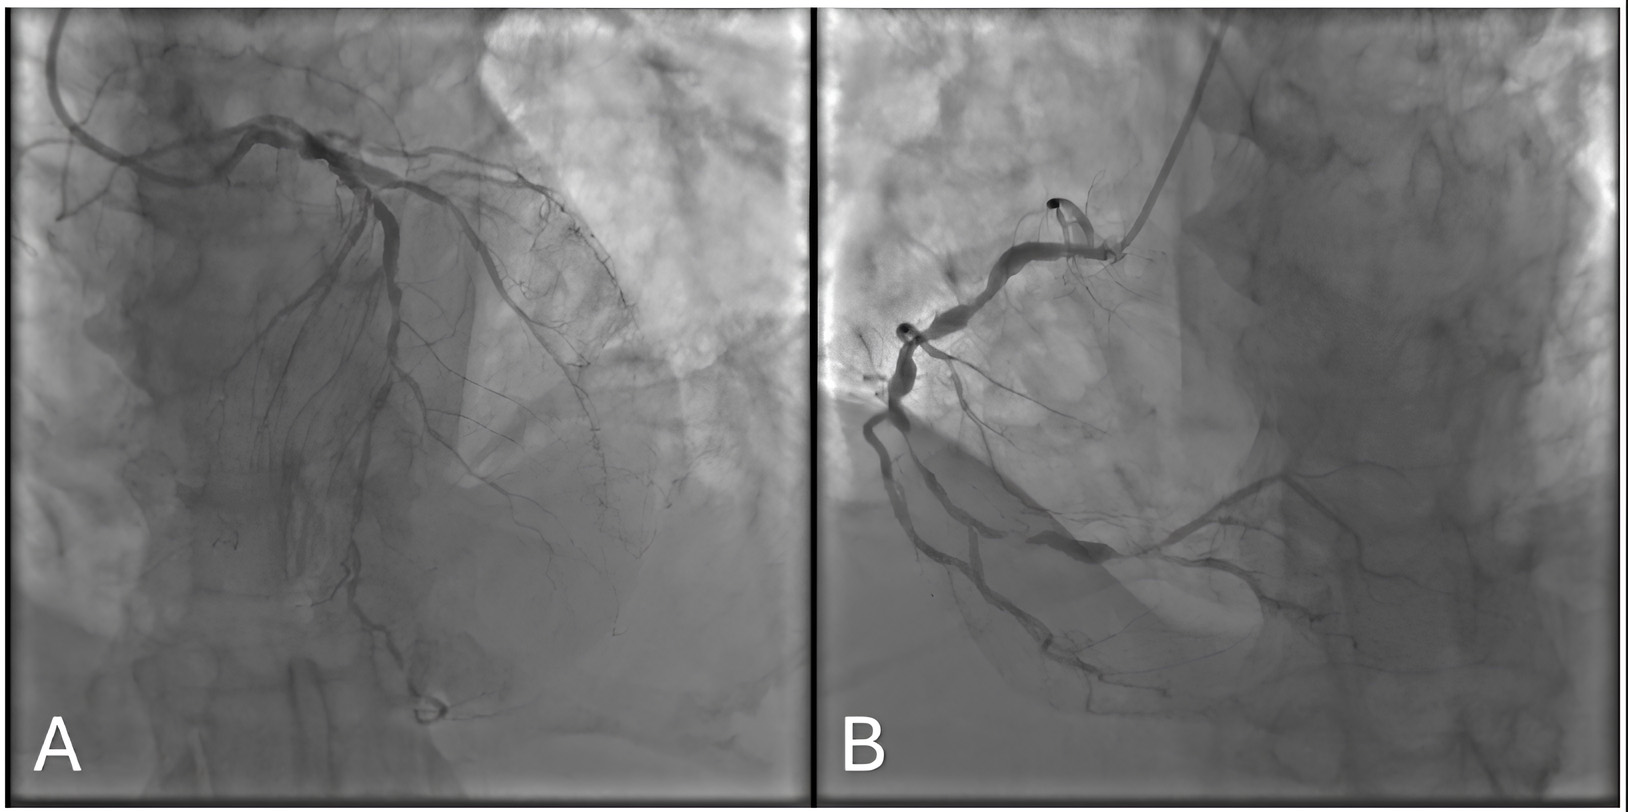

Findings: Significant multivessel lesions involving the LAD, CX (Fig. 2A), and RCA (Fig. 2B), with a valvular pathology.

Fig. 2. Coronary angiogram of the 123rd Patient. (A) Posteroanterior - Cranial 40. (B) Left Anterior Oblique - Caudal 20.

Rationale: Owing to the high operative risk and multiple comorbidities, the Heart Team opted for medical therapy.

Model Explanation: Both ChatGPT o1 and 4o recommended CABG. Although this might appear reasonable on paper, the patient’s overall status and procedural risks justified a nonsurgical approach.